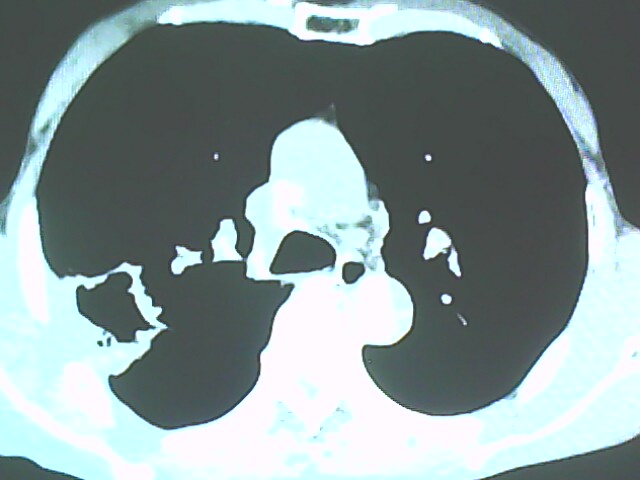

患者,男,66岁,以咳嗽、咳痰伴胸痛来就诊。

胸片提示右上肺占位病变。请各位老师看看ct。

考虑癌性空洞可能性大,空洞内壁不规则,病灶周围模糊,分叶、有毛刺

从年龄及影像特征均支持癌性空洞。

考虑右肺上叶后段周围型肺癌并癌性空洞形成。

典型癌性空洞(偏心性,壁厚薄不均,内壁不光整),周围毛刺较僵硬,且有刺突征和血管聚集征